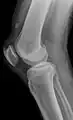

Quadriceps tendon rupture in plain X-ray

X-ray of a tear of the patellar tendon. On the left: The kneecap is pulled up. On the right: Significant dent in the soft tissue above the kneecap.